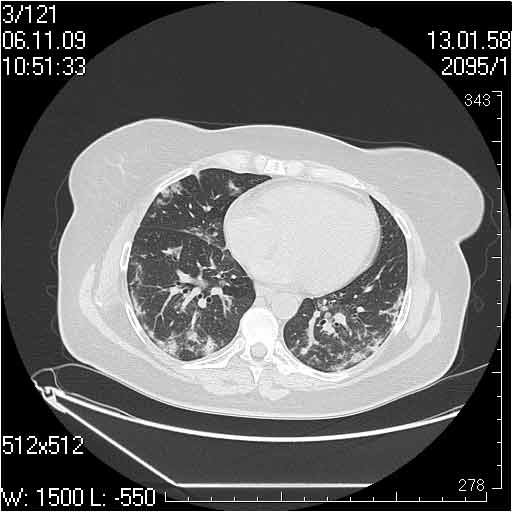

Прошу помочь правильно интерпретировать представленные изображения трех случаев с примерно одинаковой картиной.

Нами они расценены как фиброзирующий альвеолит.

Клиника во всех случаях скудная, незначительная дыхательная недостаточность, субфибрильная температура.

Случай №1

Женщина 50 лет.

Случай 1: изменения характерны для интерстициальной пневмонии (IIP/UIP idiopathic interstitial pneumonia/usual interstitial pneumonia); говорить о конкретной форме без открытой биопсии затруднительно.